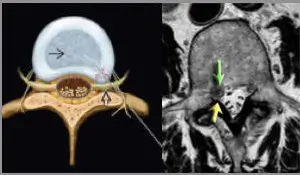

È importante consultare uno specialista in radiologia interventistica o un neurochirurgo per diagnosticare e trattare correttamente il dolore discogeno. La diagnosi può essere supportata tramite tecniche avanzate di imaging, come la risonanza magnetica (RM) o la tomografia computerizzata (TC), che permettono di osservare in dettaglio la condizione dei dischi e delle strutture circostanti.

L’approccio terapeutico varia in base alla gravità del danno al disco e alla risposta del paziente ai trattamenti iniziali. In alcuni casi, le tecniche mini-invasive come le iniezioni peridurali o la discectomia endoscopica possono offrire sollievo significativo senza necessità di un intervento chirurgico maggiore.